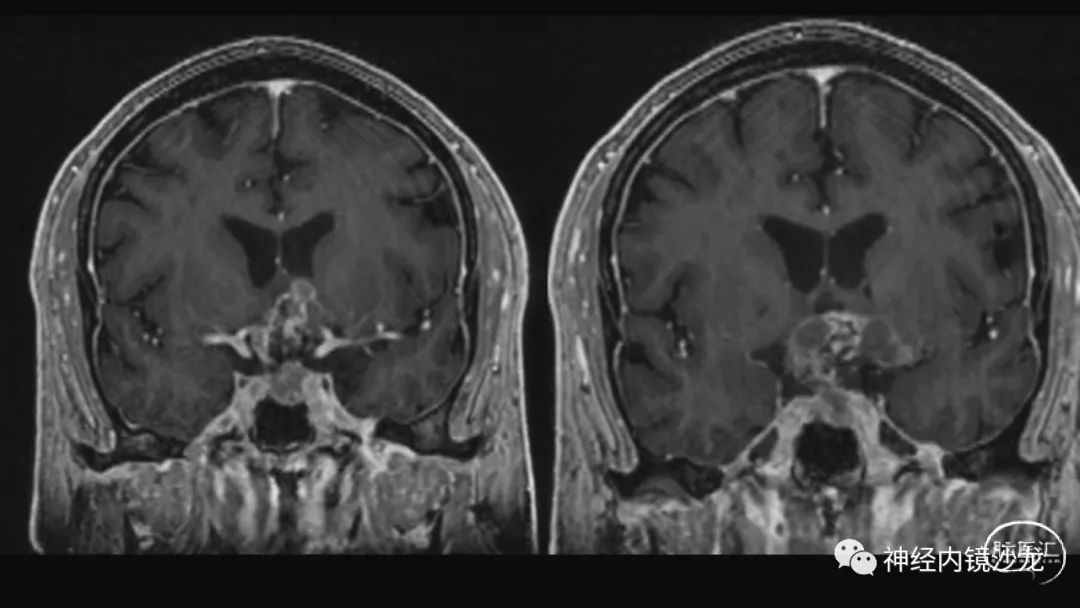

从事神经外科十余年,擅长神经外科肿瘤诊治,尤其是神经内镜微创手术治疗垂体瘤、颅咽管瘤、脑膜瘤等颅底肿瘤